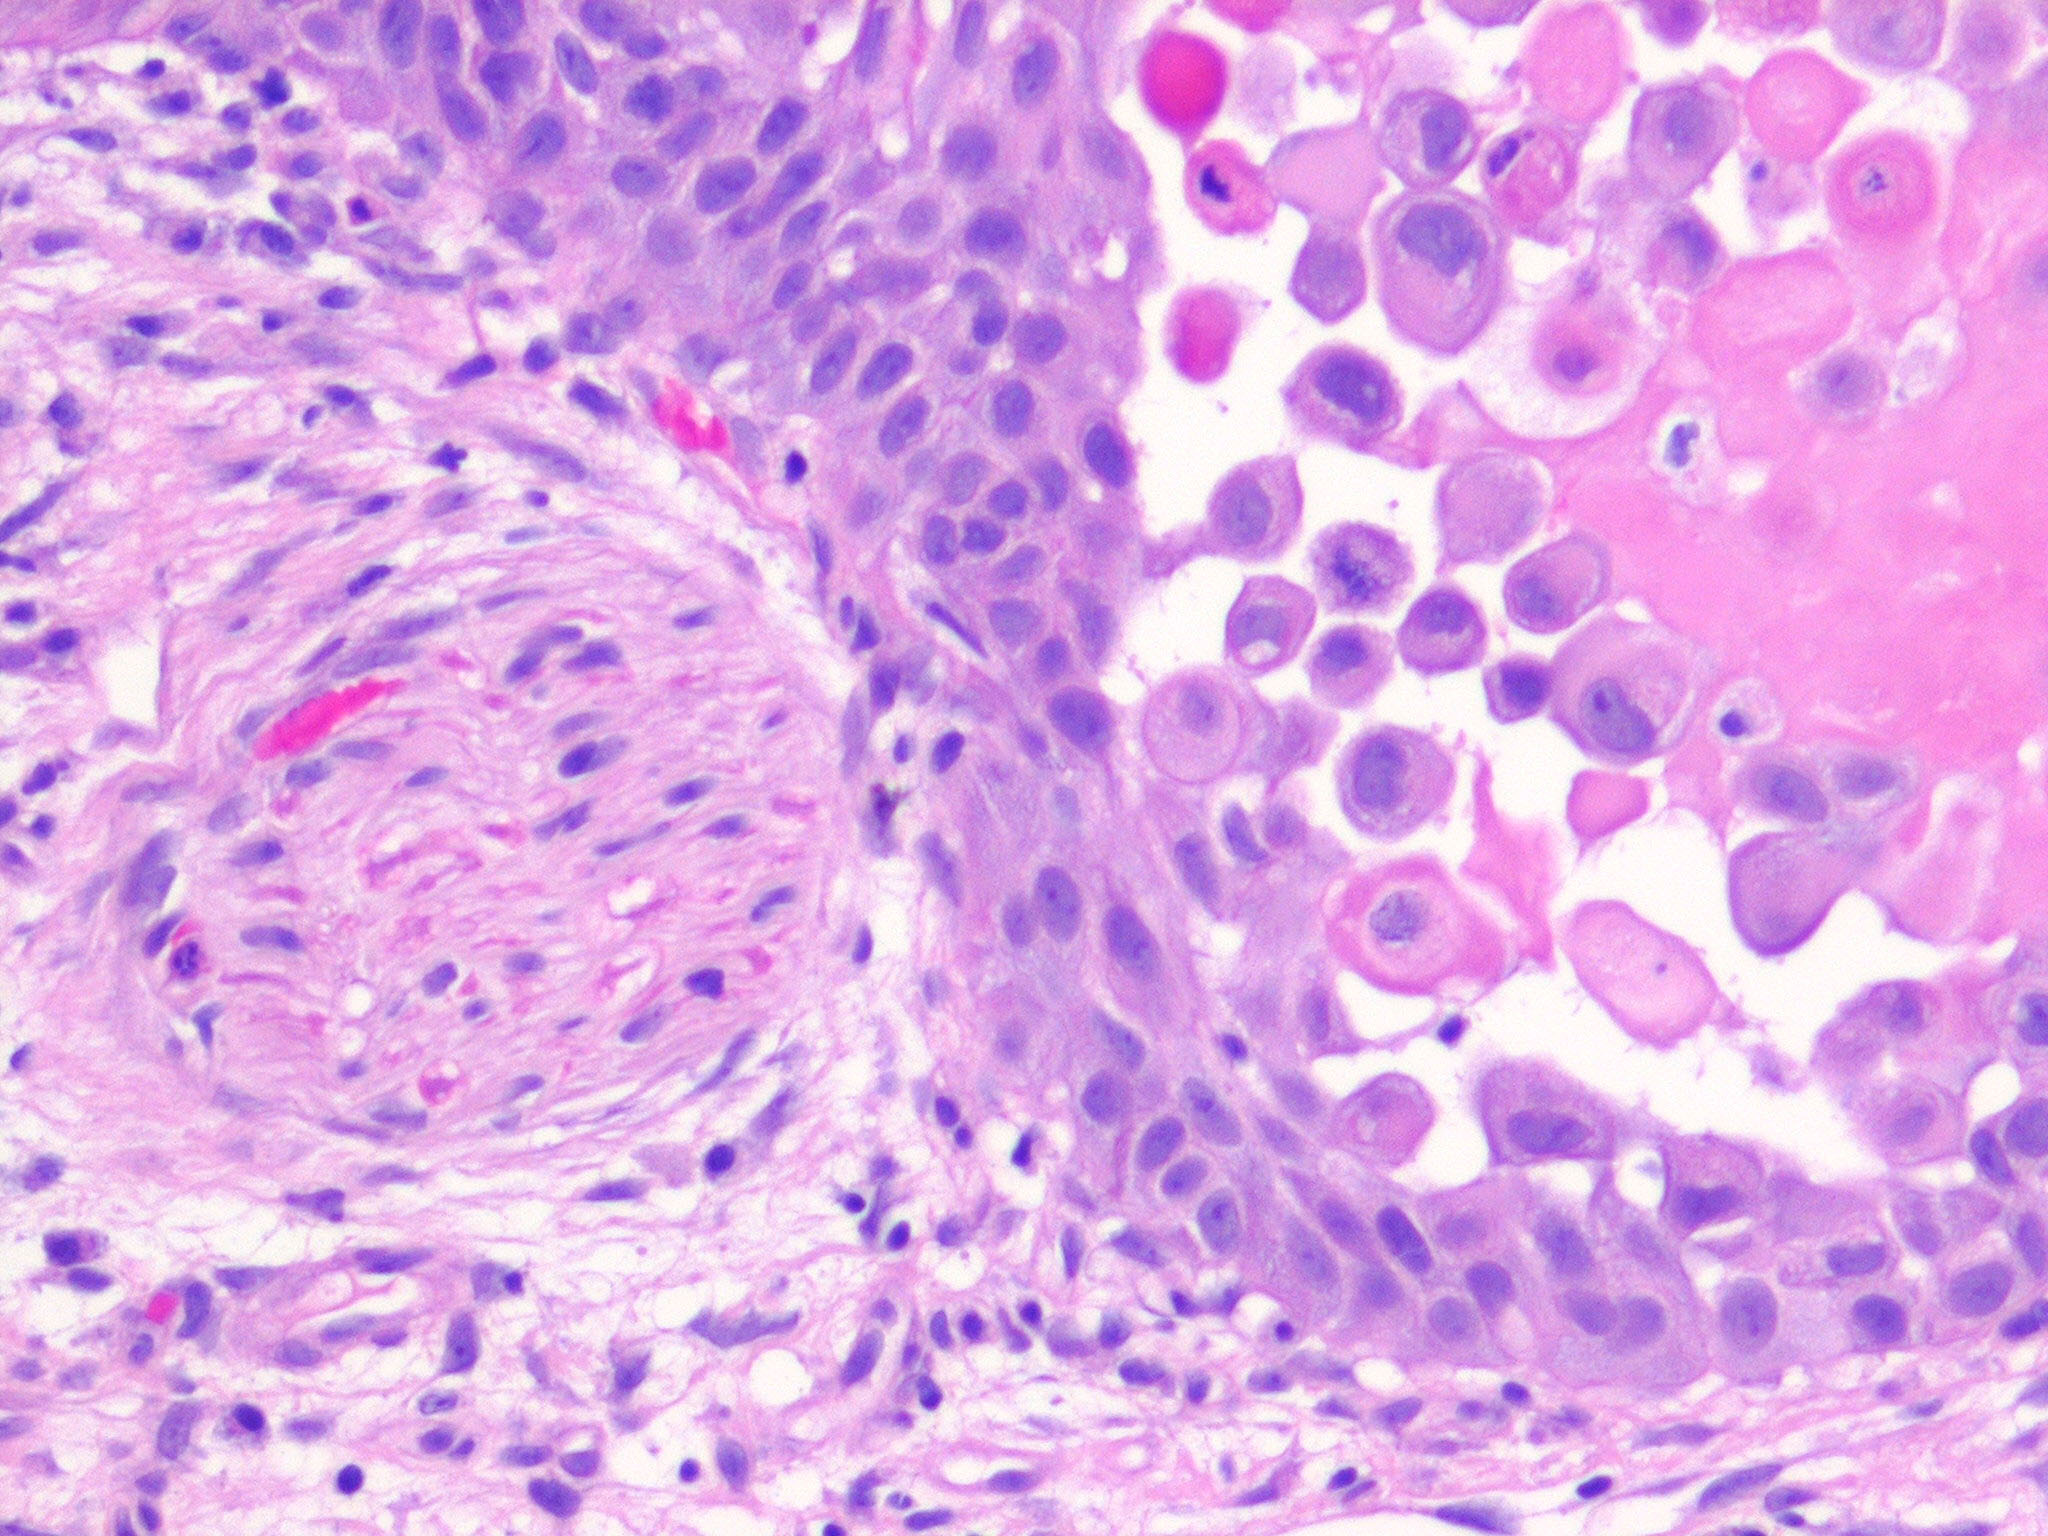

Squamous Cell Carcinoma = الكارسينوما شائكة الخلايا

OLYMPUS DIGITAL CAMERA